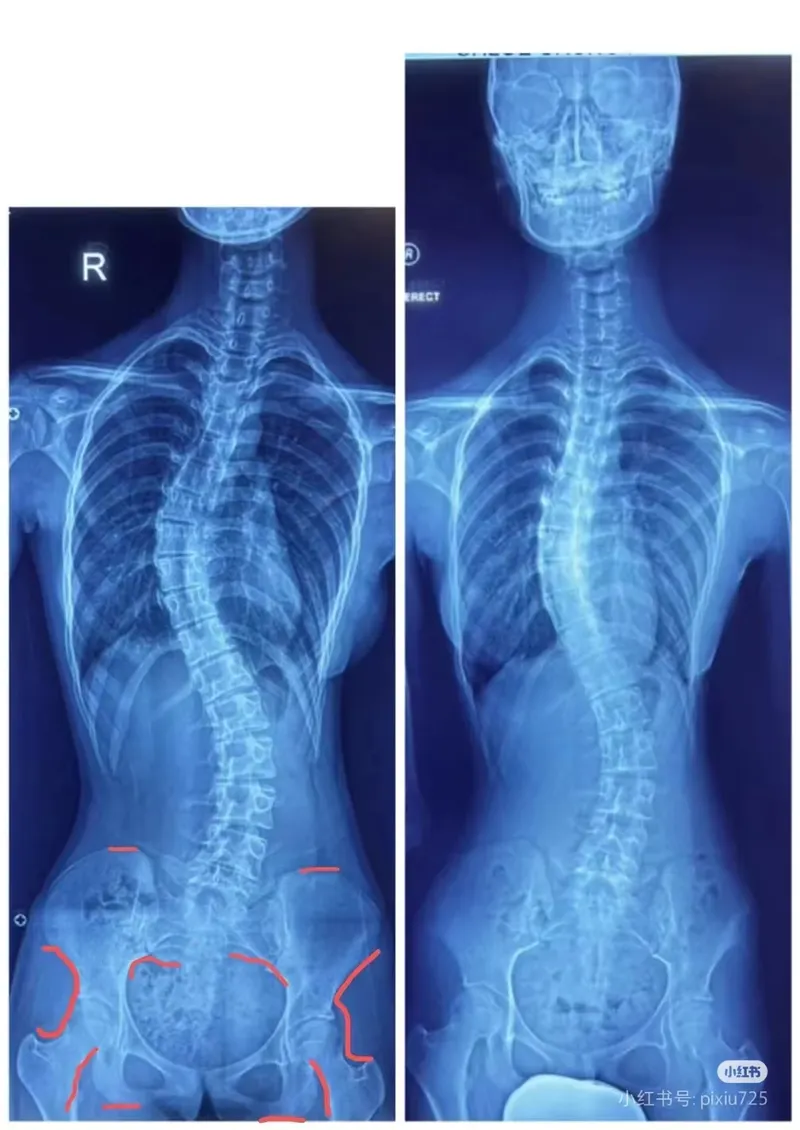

許多人不明就裡,以為側彎是脊椎的問題。

每一個側彎其實都離不開大腦神經與軀體感受器紊亂的影響,而側彎的人也絕不是練脊椎的事情,而是需要解決側彎諸多「周邊」問題:例如神經系統,感受器重建,重塑大腦與軀體的模式節律……等等。